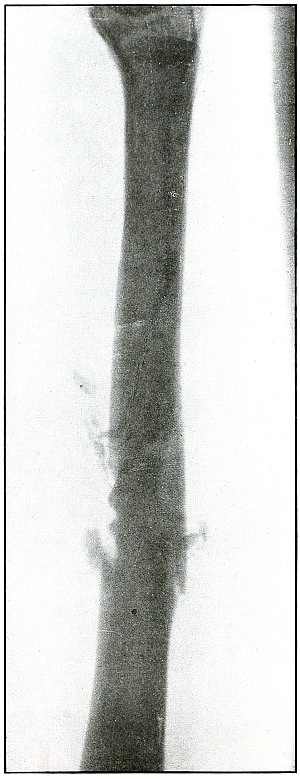

Plate 32.

[Pg 75]

Rifle—Plate 32.

UPPER EXTREMITY.

Gunshot Fracture of the Ulna.

The course of the bullet was transverse through the arm at the

junction of the middle and upper thirds from behind the radial border

externally to the ulnar border internally, striking the wall of the

medullary canal with a punching effect that partly split off short

longitudinal fragments and caused transverse and longitudinal cracks,

without separation or displacement of fragments.

The same ballistic conditions applied to cancellous tissue at the end

of the bone would probably have bored through it without fracture.

This effect is generally seen in wounds of small-caliber bullets

traveling at reduced velocity of long range.

The treatment is that of a simple fracture.

Results, in such cases without infection, could not be bad.

[Pg 76]

Plate 33.

[Pg 77]

Rifle—Plate 33.

UPPER EXTREMITY.

Gunshot Fracture of the Left Ulna.

The course of the missile was from within outward, ranging downward to

the wrist, by deflection, after striking the ulna in its upper half.

The considerable striking energy retained in a small portion of the

mass—consisting of only the nose and a little more of the jacket of

the bullet, but sufficient to fragment a large section of the bone,

and then to traverse more than half the length of the forearm—leaves

no doubt that the shot was fired at very close range, and that the

bullet was broken on a nearly resisting surface, leaving in the nose

of the bullet a striking force equal to that of the entire projectile

at long range.

The posterior surface of the forearm is next to the plate, as the

distinct outline of the styloid process of the ulna and the posterior

border of the articular surface of the radius shows. The radius and

ulna are parallel in the most natural position of supination. The

normal diameter and sharp outline of the nose of the bullet show it to

be next to the plate and on the posterior surface between radius and ulna.

Fragments of the exposed lead core of the bullet have scraped off on

the line of fracture in a manner peculiar to shrapnel wounds, but

never seen in bullet wounds in which the jacket covers all of the lead core.

The treatment is regularly conservative and without interference, as

in this particular wound, which was aseptic.

Secondary treatment may indicate correction of bone deformity.

[Pg 78]

Plate 34.

[Pg 79]

Rifle—Plate 34.

UPPER EXTREMITY.

Gunshot Fracture of the Ulna.

The ballistic conditions of the projectile causing the wound

shown in this plate are substantially those of the wound shown in

plate 32.

The wound of entrance and exit would be practically the same in

chipping off a few small fragments and causing a clean transverse

fracture without any displacement.

The bullet at long range has struck the wall of the medullary canal,

appearance.

Treatment that of a simple fracture.

Results must be good.

[Pg 80]

Plate 35.

[Pg 81]

Rifle—Plate 35.

UPPER EXTREMITY.

Gunshot Fracture of the Ulna.

The course of the bullet at long range has been anteroposterior

through the middle of the forearm, passing through the side of the shaft,

chipping off a few small fragments and causing a long oblique fracture.

The conditions were much the same as those shown in plates

28 and 29,

except that the striking energy of the projectile was somewhat

greater with the velocity of mid range.

The treatment, without infection, is that of a simple fracture.

Results will be uniformly good.

[Pg 82]

Plate 36.

[Pg 83]

Rifle—Plate 36.

UPPER EXTREMITY.

Gunshot Fracture of the Ulna.

The course of the bullet was anteroposterior through the ulna a little

above the middle of the forearm, and fairly through the long axis.

This is a bone effect much similar to those shown in plates

28, 29, and 31,

except that this condition is due to the impact of a missile, with a

still higher velocity of shorter range, imparting its energy to small

fragments of bone, which added their momentum to the destructive force

of the projectile.

No large fragments were carried along with the missile to cause any

more destruction of tissue in exit than in entrance, so that the skin

wounds, under these conditions, are about the same in appearance.

The treatment is conservative and expectant with immobilization.

Results in such cases are uniformly good.

[Pg 84]

Plate 37.

[Pg 85]

Rifle—Plate 37.

UPPER EXTREMITY.

Gunshot Fracture of the Ulna.

The course of the bullet was in an anteroposterior direction at a high

velocity of short range, which, imparting its energy to the fragments,

drove some of them through the tissues as “secondary missiles” and

caused a laceration of the wound to exist.

The longitudinal fragmentation and splitting indicates a considerable

energy of the projectile, which may have been deflected, as its long

axis was turned somewhat from the trajectory at the time of impact.

The emergency treatment is antiseptic dressing and splint immobilization.

The subsequent treatment is conservative with the removal of detached

fragments and with control of infection as the course indicates.

[Pg 86]

Plate 38.

[Pg 87]

Rifle—Plate 38.

UPPER EXTREMITY.

Gunshot Fracture of the Left Ulna.

The course of the bullet was transverse through the middle of the

forearm, striking the posterior border of the ulna.

Small fragments were broken from the posterior wall of the medullary

canal, without destroying the longitudinal continuity of the anterior wall.

The velocity of the bullet was probably that of mid-range, as the

striking energy of the impact was fairly great.

The posterior surface of the forearm lay next to the plate.

The emergency treatment is antiseptic dressing and splint

immobilization.

The subsequent treatment is that of a simple fracture,

as infection is not usual.

[Pg 88]

Plate 39.

[Pg 89]

Rifle—Plate 39.

UPPER EXTREMITY.

Gunshot Fracture of the Left Ulna.

The course of the bullet, with the velocity of long range, was

anteroposterior through the lower third of the forearm, striking the

outer side of the bone. The initial velocity of the projectile was

much reduced, as is shown by the tendency to puncture the bone without

much fragmentation.

There was no displacement of fragments as a direct result of the

impact, although muscular contraction has caused some slight

subsequent overriding.

The wounds of entrance and exit were about the same, if not quite

similar in appearance.

The emergency treatment is the conventional antiseptic dressing with

splint immobilization.

The subsequent treatment is usually that of a simple fracture,

as infection in such cases is rare.

[Pg 90]

Plate 40.

[Pg 91]

Rifle—Plate 40.

UPPER EXTREMITY.

Gunshot Fracture of the Ulna.

The course of the bullet was obliquely anteroposterior through the

lower third of the forearm, striking the radial edge of the bone with

a velocity of long range.

The wounds shown in plates 35 and 39

represent conditions similar to those causing this wound,

except that the ranges were progressively greater.

In this case the projectile exhibited a punching effect at the

point of impact, and although the lines of force are shown in

characteristically divergent fissures, the energy imparted to the

fragments—less than in the preceding cases—has not been sufficient

to separate or to displace the fragments.

The emergency and subsequent treatment is conventionally conservative,

as in the preceding cases.

[Pg 92]